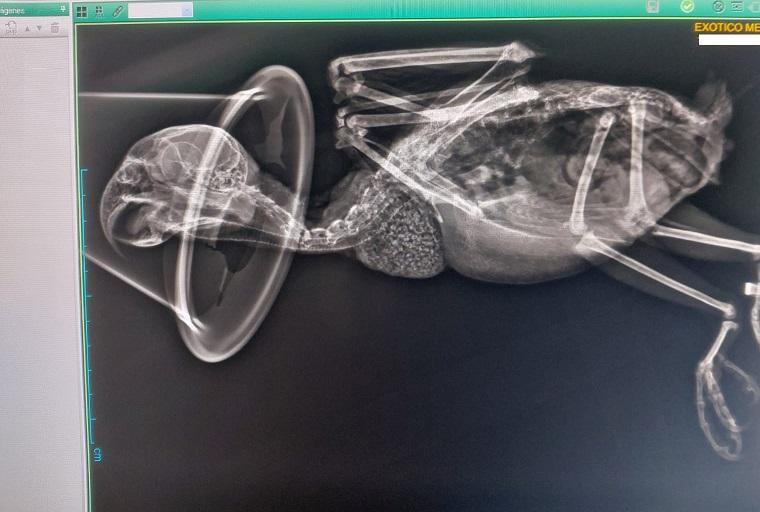

Abrimos este Teaming exclusivamente para ayudar a costear gastos veterinarios. Cada vez son más las aves que tenemos a nuestro cargo y los gastos se van sumando; revisiones a las nuevas entradas, analíticas, revisiones anuales, medicación...Más las urgencias. Cada euro cuenta y vuestra ayuda es fundamental para poder dar una vida digna a las aves a nuestro cargo. Muchas gracias por vuestro apoyo.

Destinamos la recaudación a los gastos veterinarios de la protectora, que son muchos, puesto que a las revisiones, analíticas y seguimiento de los residentes se suman los tests de enfermedades y pruebas a las nuevas entradas, sin contar con las urgencias... Con vuestra ayuda, cubriremos aunque sea una mínima parte de todos estos gastos. Gracias por estar ahí.

Estamos teniendo una entrada masiva de aves abandonadas en nuestro centro.

No paramos de recoger aves heridas.